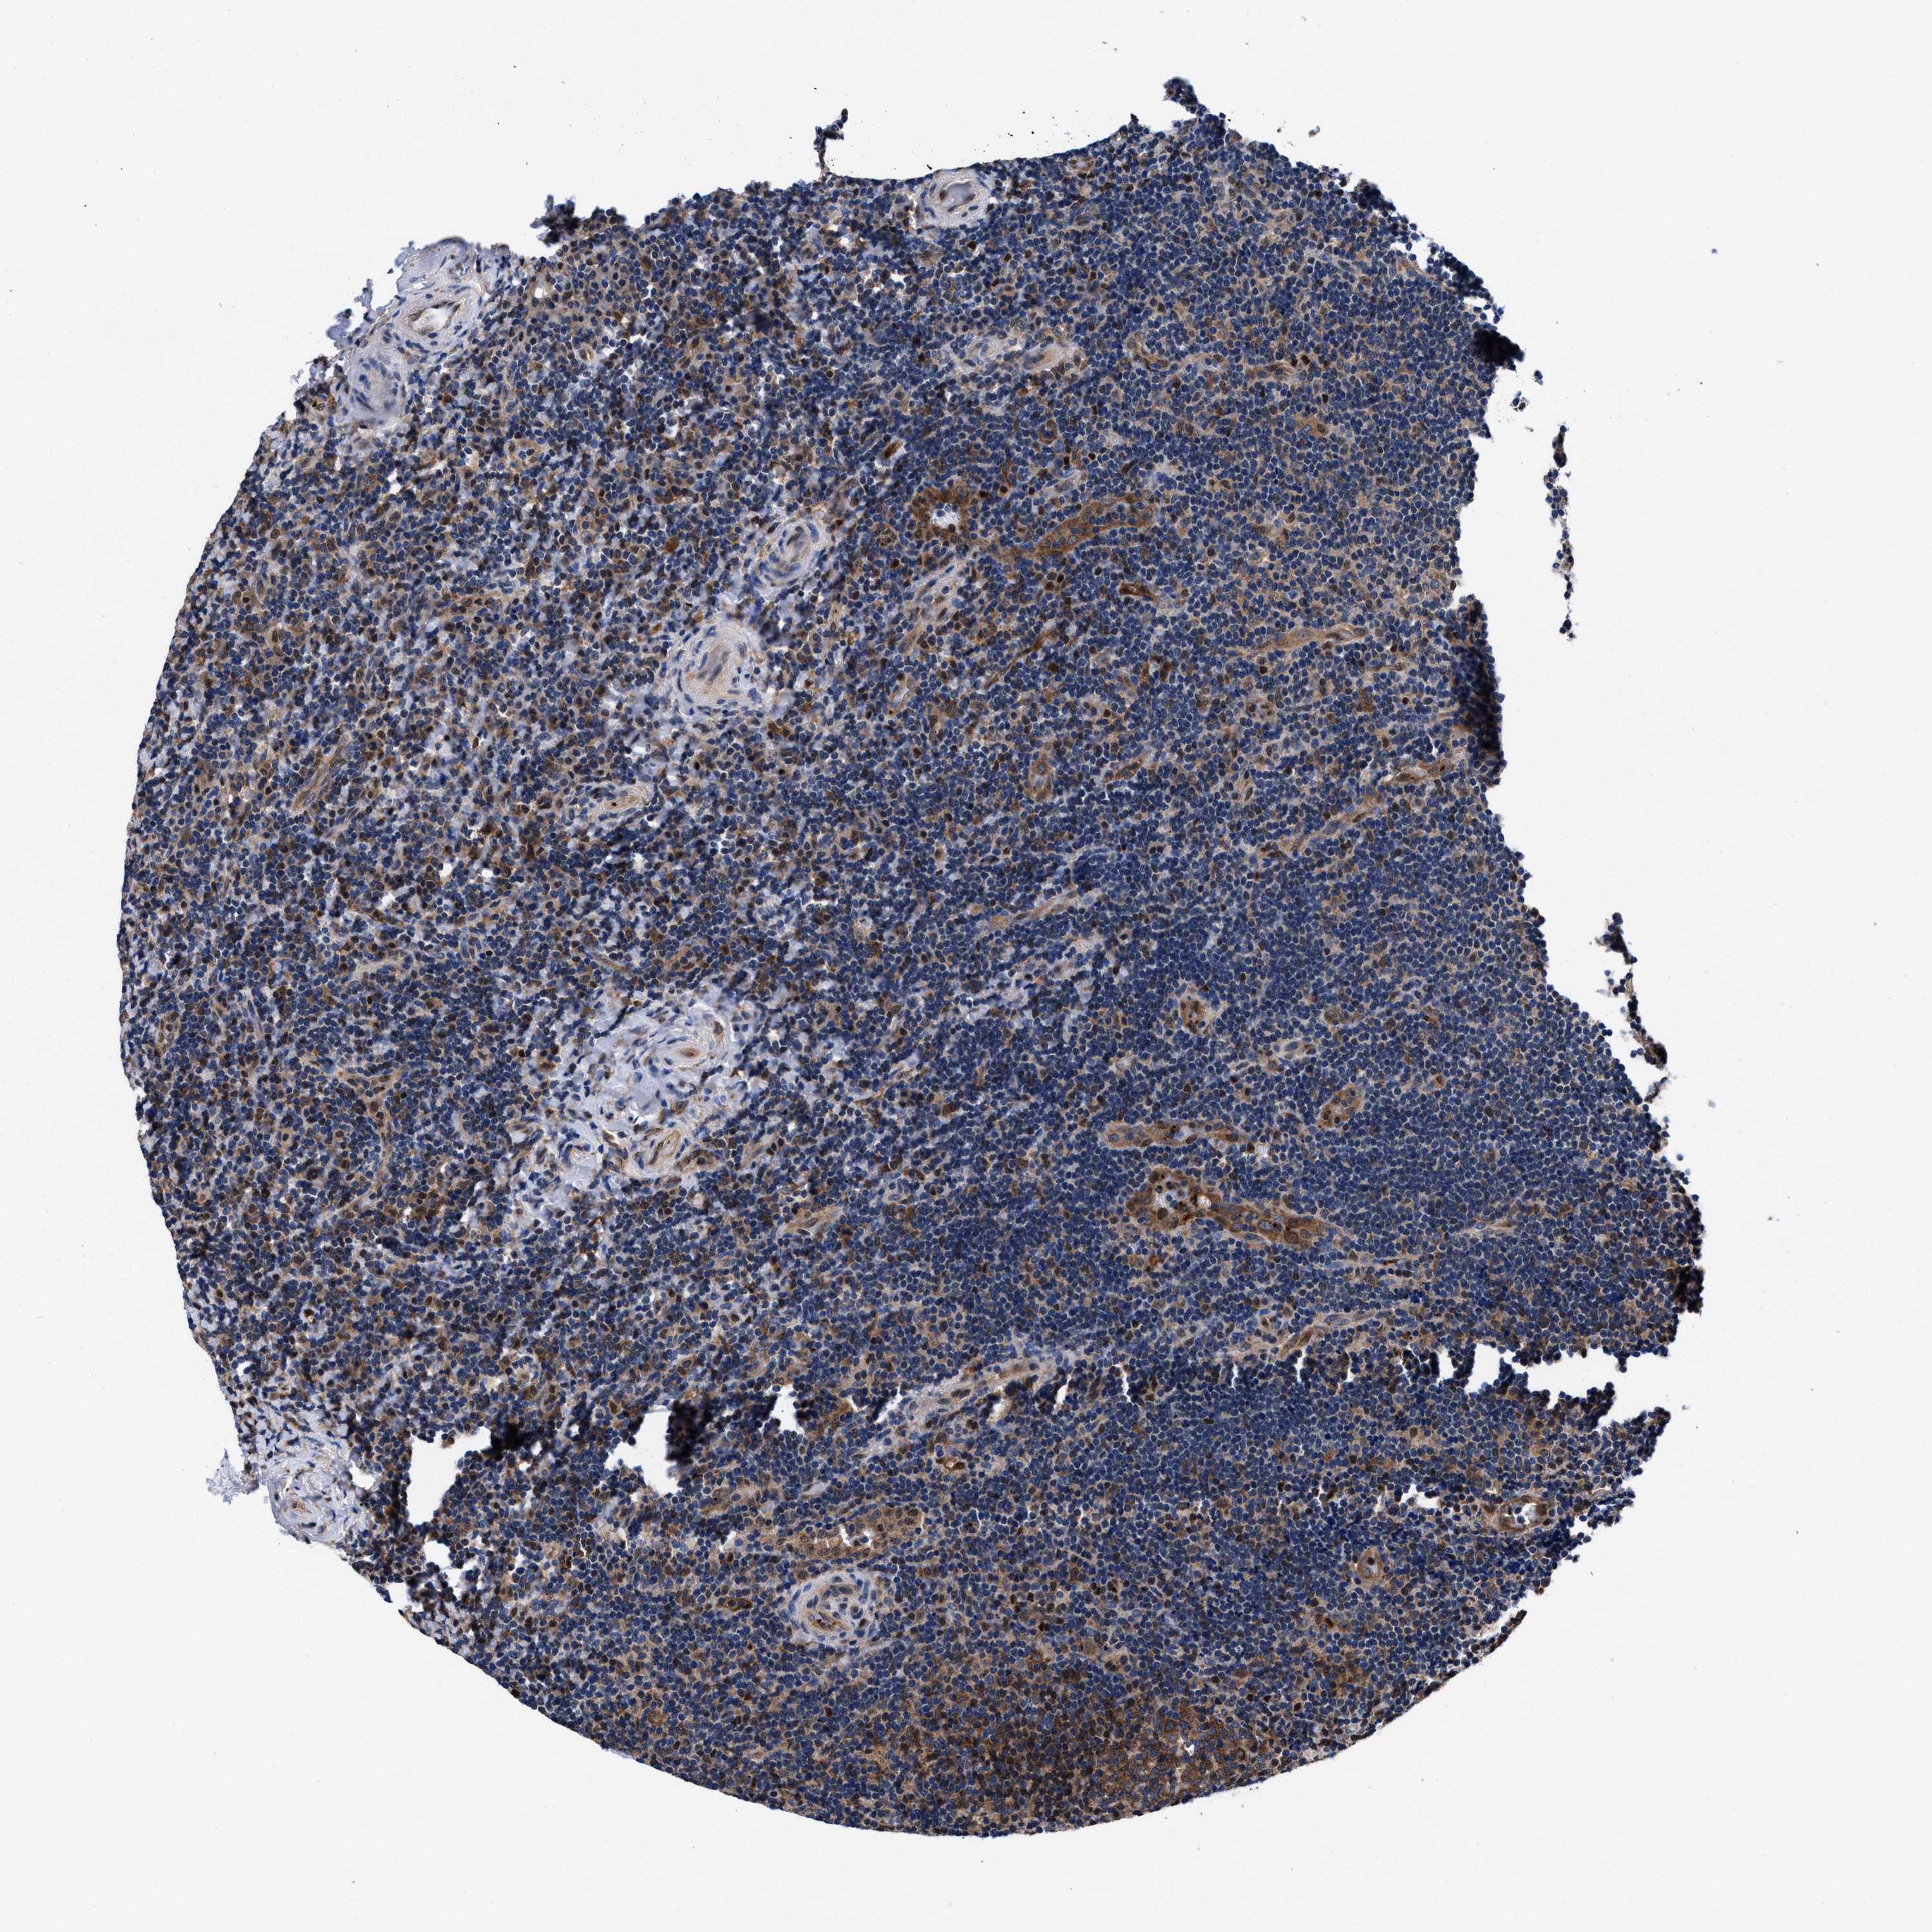

CANCER LYMPHOMA Show tissue menu

LYMPHOMA - Protein expressioni

A mouse-over function shows sample information and annotation data. Click on an image to view it in a full screen mode. Samples can be filtered based on level of antibody staining by selecting one or several of the following categories: high, medium, low and not detected. The assay and annotation is described here.

Antibody stainingi

Antibody staining in the annotated cell types in the current human tissue is reported as not detected, low, medium, or high, based on conventional immunohistochemistry profiling in selected tissues. This score is based on the combination of the staining intensity and fraction of stained cells.

Each image is clickable and will lead to virtual microscopy that enables deeper exploration of all samples and also displays staining intensity scores, fraction scores and subcellular localization as well as patient and tissue information for each sample.

HPA022434

HPA022953

HPA022959

HPA028758

CAB007783

Hodgkin's disease, NOS

Malignant lymphoma, non-Hodgkin's type, High grade

Malignant lymphoma, non-Hodgkin's type, Low grade